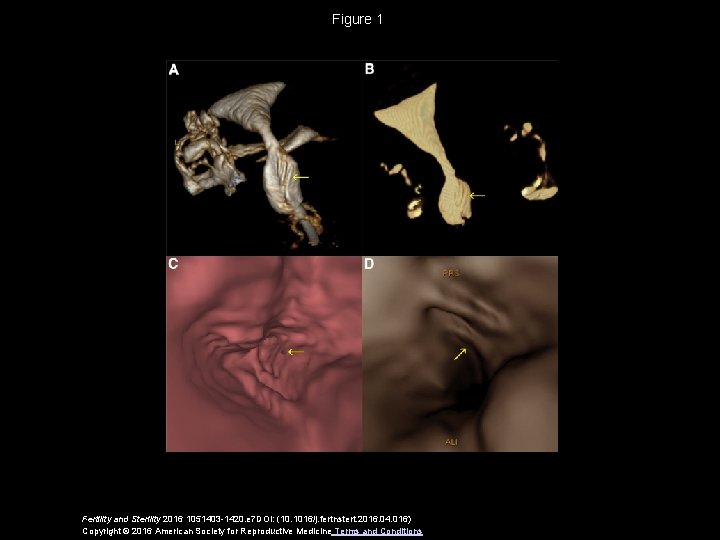

Figure 1 Fertility and Sterility 2016 1051403 -1420. e 7 DOI: (10. 1016/j. fertnstert. 2016. 04. 016) Copyright © 2016 American Society for Reproductive Medicine Terms and Conditions